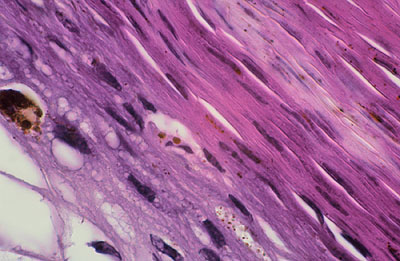

Photo 2 (Hémalun Eosine X 40) : au faible grossissement, l’épiderme revêt un aspect bleu-blanc-rouge,

bleu pour hyperplasie des couches basales, blanc pour vacuolisation des acanthocytes sous-cornés et

rouge pour parakératose de la couche cornée. Le derme est faiblement à modérément inflammatoire.

Légendes de la Photo 2 :

- Flèche bleue : hyperplasie des couches basales

- Flèche blanche : vacuolisation des acanthocytes sous-cornés

- Flèche rouge : pour parakératose de la couche cornée

- Étoile rouge : Le derme est faiblement à modérément inflammatoire